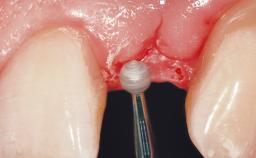

Immediate Placement of an Implant in a Maxillary Right Central Incisor Site

A 30-year-old female patient was referred to the office for the treatment of tooth 11. Her chief concern at the initial visit was to inquire, “Why is my tooth pink?” Upon clinical examination, it was determined that tooth 11 had a previous history of trauma and that the clinical crown had become noticeably pink in color as a result of internal resorption. This diagnosis was confirmed radiographically, indicating a large radiolucency involving the central and distal portions of the clinical crown. It was determined that restoration of this tooth was not possible, and that extraction was indicated. The presence of a mid-line diastema, which the patient wanted to reproduce, directed the treatment plan for tooth replacement utilizing a dental implant.

Soft Tissue Anatomy Intact Defective

Soft Tissue Contour and Volume Ideal